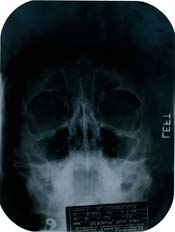

හොලිවුඩයේ ප්ලාස්ටික් ශල්ය වෛද්ය මයිකල් ගර්ඩින්ගේ වෛද්ය වාර්තා රැසක්ම මීට අඩංගුය. වෙන්දේසියට වෛද්ය වාර්තා ඉදිරිපත් කරන්නා නම හෙළි කිරීමට අකැමැතිය. වසර 1950 ට පසු මොන්රෝ නිකටට කාට්ලේජ බද්ධයක් කර තිබේ. හව් ටු මැරි අ මිලියනියර් (1953), ද සෙවන් ඉයර් ඉච් (1955), සම් ලයික් ඉට් හොට් (1959) තිරගත කෙරුණේ මේ කාට්ලේජ බද්ධයට පසුවය. කිසිවකු ඇය ප්ලාස්ටික් සැත්කමක් කළ බව දැන සිටියේ නැත. එක් දහස් නවසිය පනස් ගණන්වල ප්ලාස්ටික් සැත්කම් නැවුම් අත්දැකීමකි. මොන්රෝගේ පපු පෙදෙසේ එක්ස් කිරණ ඡායාරූප 3 ක් 2010 වෙන්දේසියේදී ඩොලර් 45,000 කට අලෙවිකර තිබේ. පසුව මොන්රෝගේ නාසයට ද ප්ලාස්ටික් සැත්කමක් කර ඇත. මොන්රෝ සුදු රුධිර සෛල ඌනතාවෙන් පීඩා වින්දාය. ඇය ගර්භාෂයෙන් පිටත පිළිසිඳ ගැනීමකට ද ලක් වී සිටියාය.

මැරිලින් මොන්රෝ අදටත් සරාගී සුරූපිනියන් අතරේ පෙරමුණේය. අග බිසවක නොවුණත් ඇය

රජුන්ගේ ද හදවතෙහි රැජන වූයේ මන මෝහනීය රූසපුව නිසාමයි. එහෙත් මේ රුව පිටුපසත්

ප්ලාස්ටික් සැත්කමක රහස සැඟ වී ඇති බව සිතන්නට පුළුවන් ද? ලබන මාසයේදී මැරිලින්

ලොවෙන් සැඟ වූ ඒ රහස හෙළි කෙරෙයි. ඇයගේ ඡායාරූප ඇතුළු එක්ස් කිරණ ප්ලාස්ටික්

සැත්කමට අදාළ ලියකියවිලි නොවැම්බර් මාසයේදී වෙන්දේසියට ඉදිරිපත් කෙරේ.